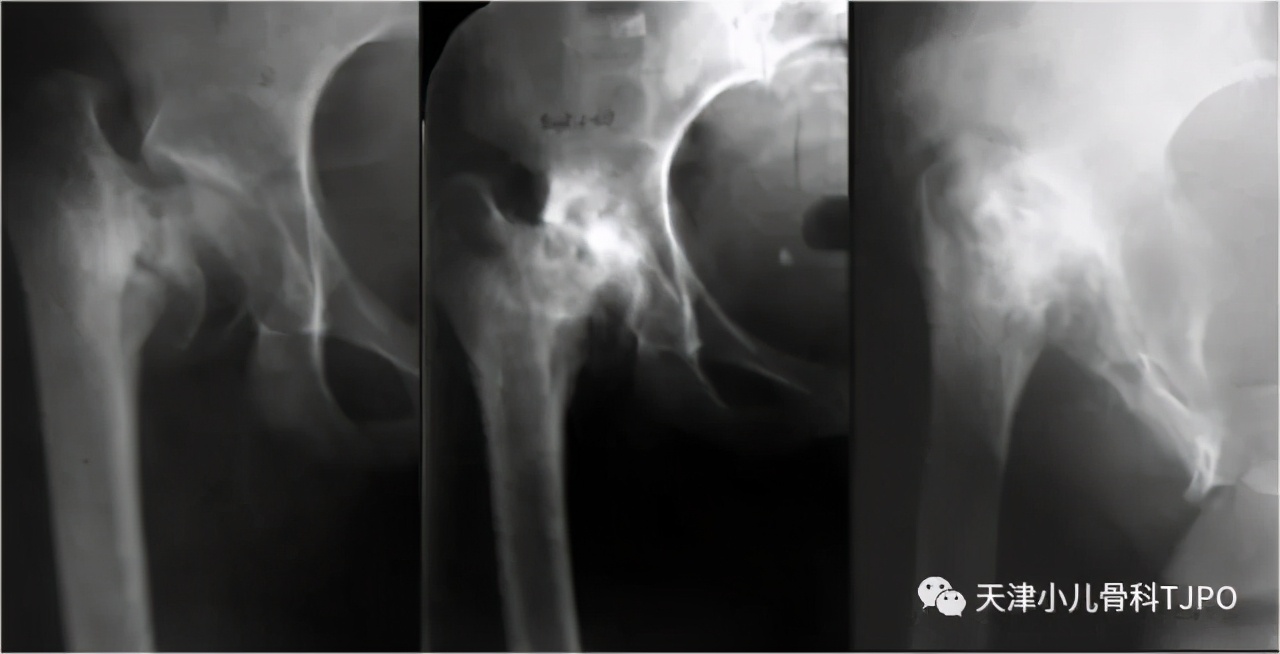

男孩,5岁,就诊前半年家长发现孩子走路“摇摆”,但是不痛。“骨盆正位X线片”显示:双侧股骨颈干角减小,干骺端与股骨头骺间增宽、碎裂的透亮带,股骨颈内下方不规则骨化。经验不多的医生可能会误诊为股骨颈骨折不愈合或慢性股骨头骺滑脱。

这其实是一例发育性髋内翻(也称为先天性髋内翻)的病例。在1岁的X线片中已经可看到左侧股骨颈内侧形态有异常。股骨颈与头骺间增宽的透亮带其实就是增宽的骺板线,容易被误认为骨折线,股骨颈内下方的骨化不规则三角形区域是部分病例的特征性表现。

发育性髋内翻是一种以原发性软骨缺陷为特征的发育性疾患,发病率约为1/25000。X线片表现为股骨颈干角减小、股骨颈变短、大转子相对上移及患侧下肢短缩(图1),畸形在出生时通常不明显,多在站立行走后才逐渐出现。具体病因不明,可能是由于股骨颈内侧软骨钙化的原发性缺陷,而这一缺陷使股骨颈内侧支撑减弱,在肌力和体重的压力下,机械软弱的股骨颈会出现进行性内翻成角,而股骨头骺会经股骨颈的薄弱区向下滑移。称之为发育性髋内翻,正是基于畸形随儿童生长发育逐渐进展的特征。